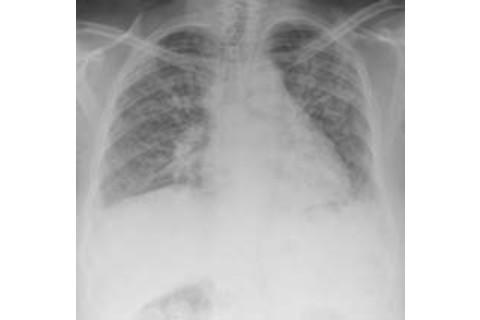

Image: iStockphoto